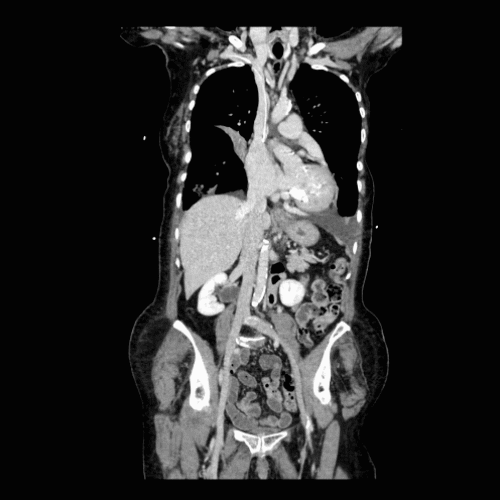

A patient experiencing shortness of breath, fatigue, and palpitations was referred to the 3DQ Lab for Transcatheter Mitral Valve Replacement (TMVR) evaluation. Imaging revealed a severely calcified mitral valve, a common cause of mitral regurgitation. This calcification stiffens the valve, preventing it from closing completely and thereby impeding efficient blood flow through the heart.

The TMVR evaluation begins with a 3DQ Lab technologist obtaining the imaging study for this patient, which is a cardiac-gated CT Angiogram (CTA) of the chest, abdomen, and pelvis, with contrast to visualize blood flow. Cardiac gating synchronizes the image acquisition with specific phases of the heart’s cycle, allowing for a clearer and more detailed view of the heart’s structure and function.